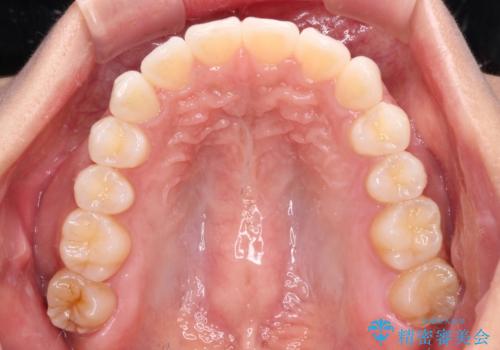

- 前に出ている上顎前歯が気になるとのことで来院された患者様です。

インビザラインを用い、IPR(歯と歯の間を削る)と歯列全体を後方に移動させることで、可能な限り前歯の突出感を改善することとしました。

元々の歯列も整っており、横顔の印象の出っ歯ではなかったため、仕上がりに満足できない可能性があると心配しておりましたが、口が閉じやすくなり、患者様には大変満足していただきました。